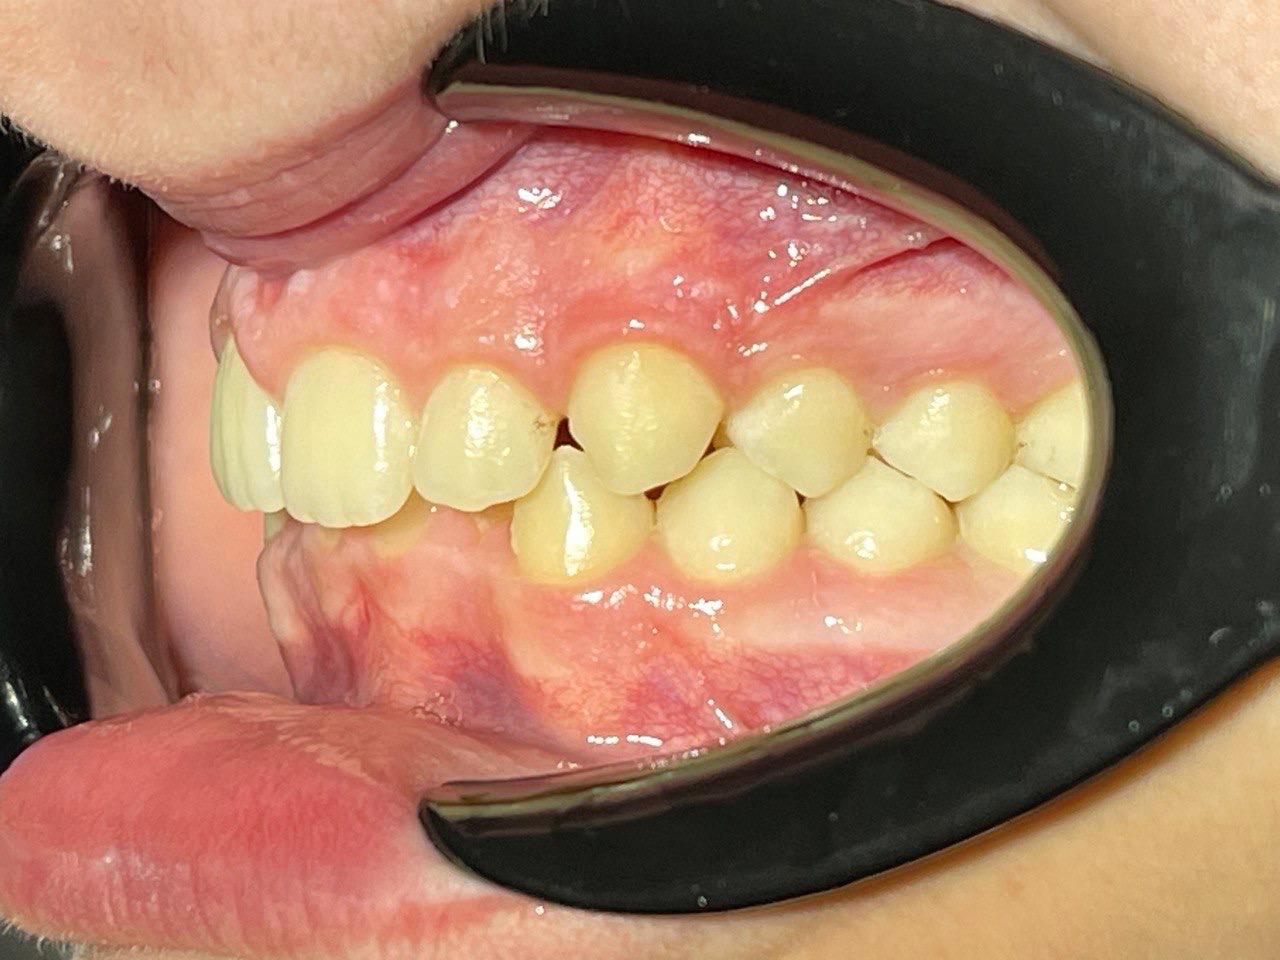

Выявленные проблемы

• Дистальная окклюзия

• Дефицит апикального базиса

• Сужение зубных рядов

• Вестибулярное положение клыков

• Скученность во фронтальных и боковых отделах

Брекет-система Pro